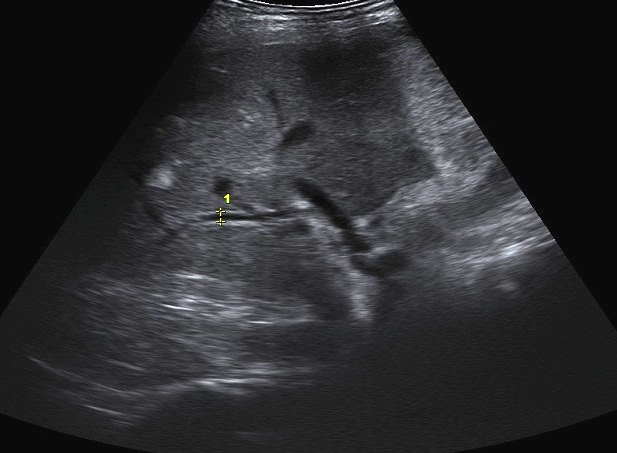

Echographie :

Est technique de choix de premiere de l'intention

dans des cas avait de douleur abdominale en plus avec une

bilan d'ictere de la maladie ce qui en suspecte d'une

adenocarcinoma du pancreas . Image

echo graphique direct du tumeur est image

lesionaire de masse hyperechogene a bord flou non de

contour de la glande . Technique echographique est moindre

de recherche dans les cas de petite tumeur a inferieure de

2mm et sa sensibilite de recherche varie de 55-90% des cas .

Image echographique indirect de adenocarcinoma de la tete du

pancreas sont : Une dilatation du canal de Wirsung de plus

de 3mm en amont du lesion , dilatation de voie biliaire

principale en associe dilatation des voies biliaires intra

hepatique sur les cas tumeurs cephaliques , une atrophie du

parenchyme pancreatique en amont et un pseudokyste en amont

( pancreatite aigue )